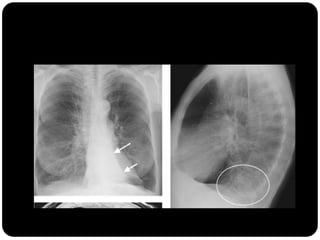

 Brônquios principais originam-se da traquéia

na carina;

 Brônquio direito: ângulo mais obtuso com o

eixo longo da traquéia;

 Direito(2,2cm) mais curto que o

esquerdo(5cm);

BPD: BLSD

BI - BLM

BI – BLID

BPE: BLSE

BLIE